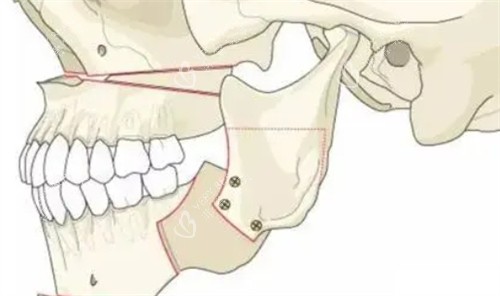

五、关节检查:别让"咔嗒"声毁了手术!

"我术前关节总响,医生说有颞下颌关节紊乱,必须先治疗!"29岁的小周差点因为忽略这个检查,导致术后无法正常张嘴。

关节检查查什么?

张口度:正常应>3.5cm

关节弹响:频率、位置、性质

关节疼痛:静息痛/咀嚼痛

关节盘位置:是否移位

MRI是金标准,能清晰显示:

关节盘是否穿孔

骨面是否侵蚀

关节腔是否有积液

医师建议:有颞下颌关节紊乱的患者,需先3-6个月保守治疗(如咬合板),待症状稳定后再手术。